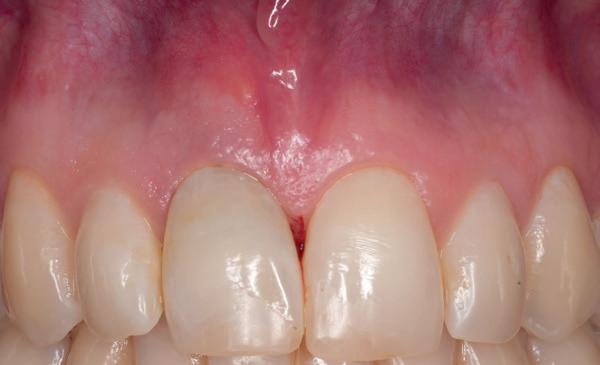

Zitting 3 Scanafdruk

Voordat er een brug van zirkoonoxide gemaakt kan worden, dient met een tijdelijke brug de stand van de elementen, de curve, de occlusie en articulatie getest te worden. Hiervoor werd gekozen voor een kunststof gefreesde brug van PMMA. Daartoe werd een intraorale scan (Trios 3, 3Shape) gemaakt van de edentate bovenkaak, scan met scan abutments op de implantaten, scan van de onderkaak, scan van de prothese en een beetscan links en rechts met de prothese in (afbeelding 7 en 8). Daarnaast werden volgens een foto protocol portretfoto’s van het front, zij, boven, onder en rustpositie lip genomen. Op basis van de foto’s werd besloten om met een beetverhoging van 2 mm te werken. De technicus zette de foto’s en prothese over elkaar in de CAD-software (Exocad, Align) en stuurde de behandelaar een 3D-bestand van de tijdelijke brug met schroefgaten, die na goedkeuring werd gefreesd (afbeelding 9 en 10).

patiënt kon 2 maanden functioneren met de tijdelijke brug, waarna een kort consult werd gepland om te bespreken of hij tevreden was met de esthetiek en functie. Voor de patiënt hoefde niks veranderd te worden (afbeelding 11-14).

14. Portretfoto met tijdelijke brug

20. Frontaanzicht brug